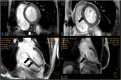

Dengue disease is found worldwide and has been spreading exponentially in the past decades. Severe forms affect about 2% of patients, sometimes leading to organ failure. Recent studies have shown that fulminant dengue myocarditis is more common than previously thought, and fatal cases have been reported. The treatment of fulminant dengue myocarditis remains supportive and is very challenging in cases of cardiogenic shock. Here, we describe four cases presenting with fulminant dengue myocarditis treated with extracorporeal membrane oxygenation, among two survived.